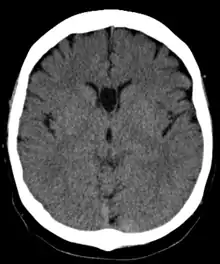

Cave of septum pellucidum

The cave of septum pellucidum (CSP), cavum septi pellucidi, or cavity of septum pellucidum is a slit-like space in the septum pellucidum that is present in fetuses but usually fuses during infancy. The septum pellucidum is a thin, laminated translucent vertical membrane in the midline of the brain separating the anterior horns of the right and left ventricles. It lies posterior to the corpus callosum. Persistence of the cave of septum pellucidum after infancy has been loosely associated with neural maldevelopment and several mental disorders that correlate with decreased brain tissue.[1][2][3][4][5]

The cave of septum pellucidum is bounded anteriorly by the genu of the corpus callosum, superiorly by the body of the corpus callosum, posteriorly by the anterior limb and pillars of the fornix, inferiorly by the anterior commissure and the rostrum of the corpus callosum, and laterally by the leaflets of the septum pellucidum.[6]

In prenatal development of the fetus, the laminae of the septum pellucidum separate to form a small cavity – the cave of septum pellucidum. This is an important normal structure to identify in the sonographic assessment of the fetal brain. In post-natal life, the laminae of the septum pellucidum usually fuse, which obliterates the cavum. The cavity contains cerebrospinal fluid (CSF) that filters from the ventricles through the septal laminae.[7]

There are individual differences in the degree of CSP; whereas some have complete closure of the cavum, others present with a small degree (4–6 mm wide, in the coronal plane) of incomplete closure.[4] The most common type of CSP is noncommunicating; that is, it does not connect to the brain's ventricular system. Because of this lack of communication, the previous use of the term "fifth ventricle" is no longer used, and the fifth ventricle is the name often used for the terminal ventricle.